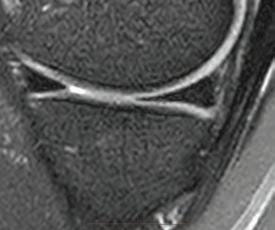

the line? Dr David Colvin 52 Imaging of the knee Dr Gavin Watson 55 Shoulder instability surgery: do it right, do it once Dr William Blakeney 61 A new health paradigm Dr